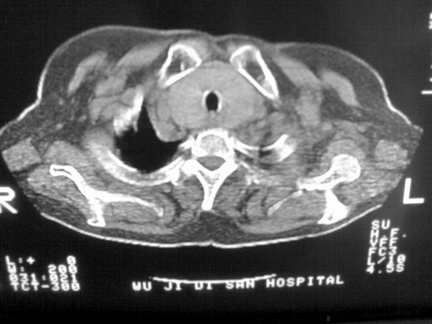

标题: CT13142:女 80 胸闷、气短、1w [打印本页]

标题: CT13142:女 80 胸闷、气短、1w

右肺炎性变,双侧甲状腺肿,胸膜肥厚。

右肺炎性变

双侧胸腔积液

缩窄性心包炎

左室为主的心脏增大。

胸膜肥厚,

气管,支气管软骨钙化。

右肺感染;双侧胸腔少量积液,心影增大,可能与心功不全有关;胸内甲状腺肿。

右肺炎性变,双侧甲状腺肿,胸膜肥厚,心影增大考虑心功能不全.

胸内甲状腺肿;右肺感染;双侧胸腔少量积液。

胸内甲状腺肿;右肺中叶感染;双侧胸腔少量积液;心影增大,考虑有心功能不全。